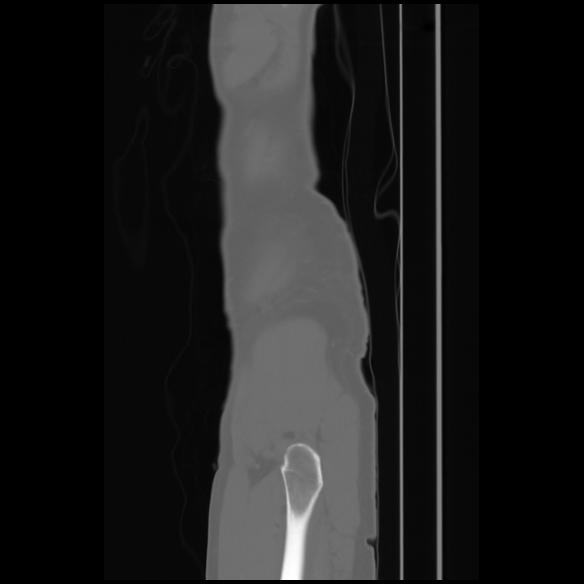

7 CUERPO,CE,Sagittal,3.000,CUERPO,Sagittal,